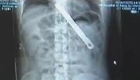

男子赌气吞下18厘米刀片